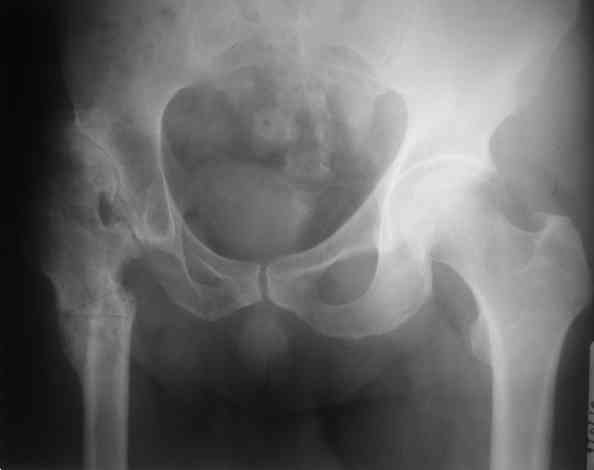

Уважаемые коллеги, без Р-граммы таза нельзя рекомендовать что-н.конкретно, представьте себе, что второй сустав находится в анатомическом положении,тогда позиция шейки протеза на оперируемой стороне будет примерно на уровне малого вертела, и тогда вам придется так укоротить б/вертел, что вы можете остаться без него.... Это очень не простые операции и нельзя без оценки всего таза что-н.советовать, во всяком случае мне так кажется